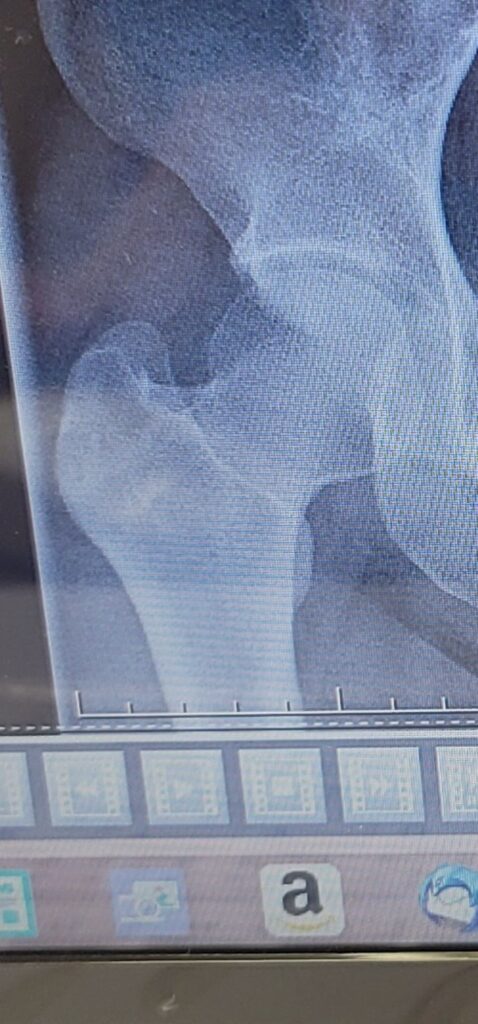

レントゲンを撮って持ってきてくれました。